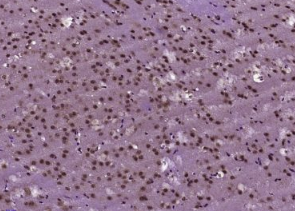

多聚甲醛固定,石蜡包埋(小鼠脑);用柠檬酸钠缓冲液(pH6.0)煮沸15min后获得抗原;用3%过氧化氢阻断内源过氧化物酶20分钟;阻断缓冲液(正常山羊血清)37℃30min;用(BNC1)多克隆抗体进行抗体孵育Tibody,未结合,1:400,4°C下过夜,然后根据SP试剂盒(兔子)说明和DAB染色进行操作。